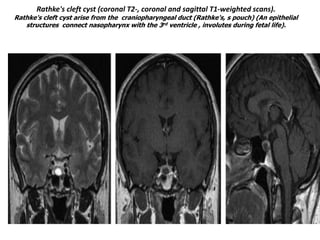

Rathke's cleft cyst (coronal T2-, coronal and sagittal T1-weighted scans).

Rathke's cleft cyst arise from the craniopharyngeal duct (Rathke's, s pouch) (An epithelial

structures connect nasopharynx with the 3rd ventricle , involutes during fetal life).